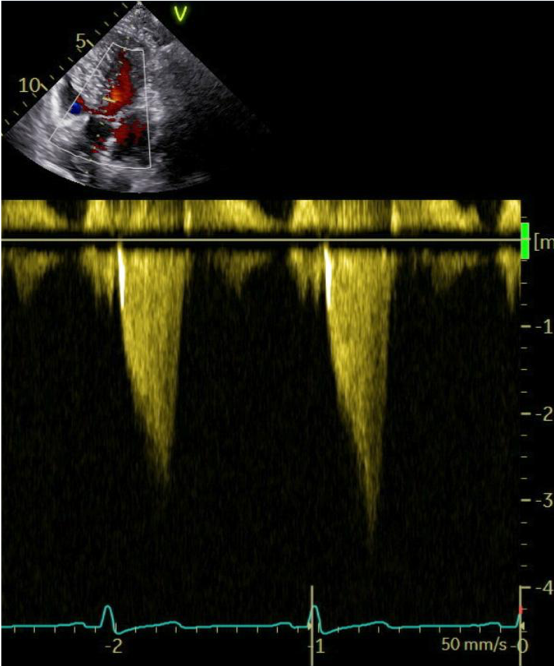

Because of a persistent elevated LVOT-gradient of 51 mmHg (Image 1a) and ongoing symptoms (NYHA-Class III), we decided to initiate additional treatment with the first-in-class myosin inhibitor mavacamten.